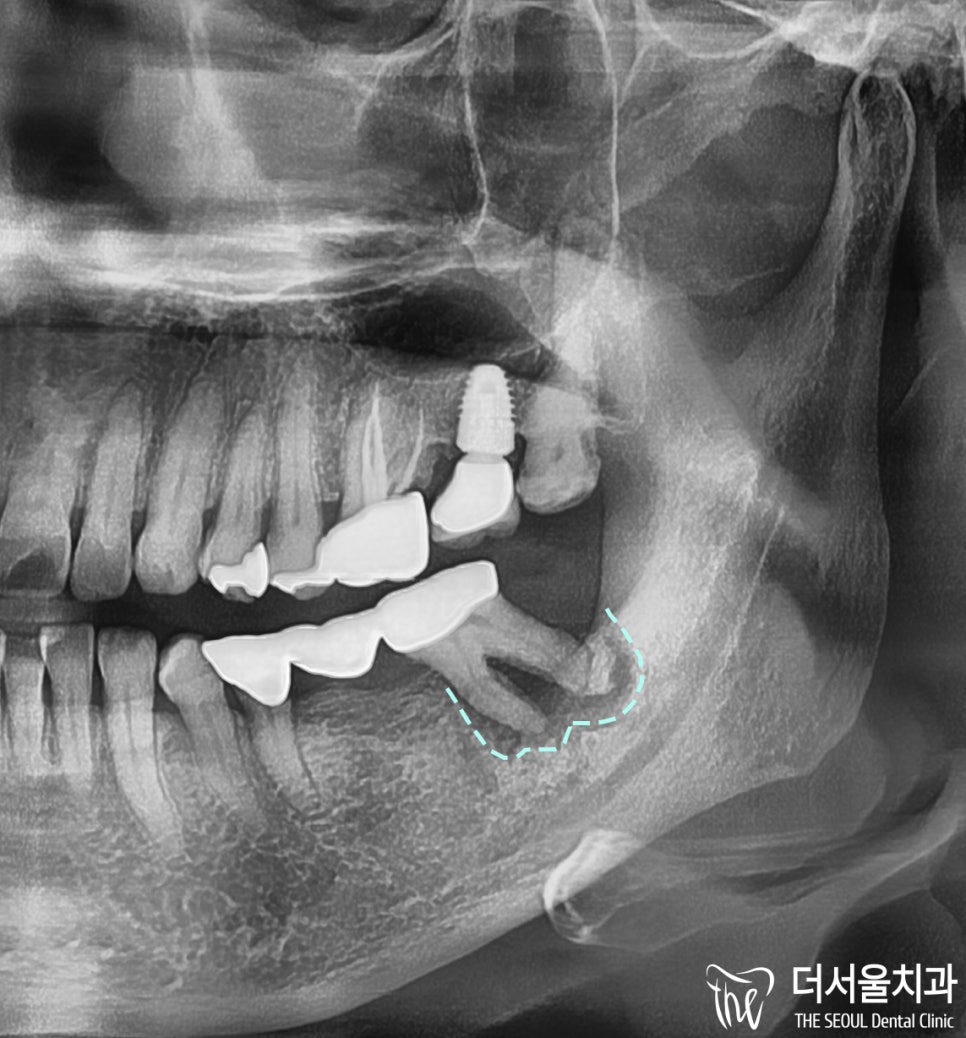

파노라마 사진을 보면,

어금니 뿌리 주변이 녹은 것을 확인할 수 있으며

확대된 사진으로 보면

‘더욱’ 명확하게 확인해 볼 수 있었습니다.